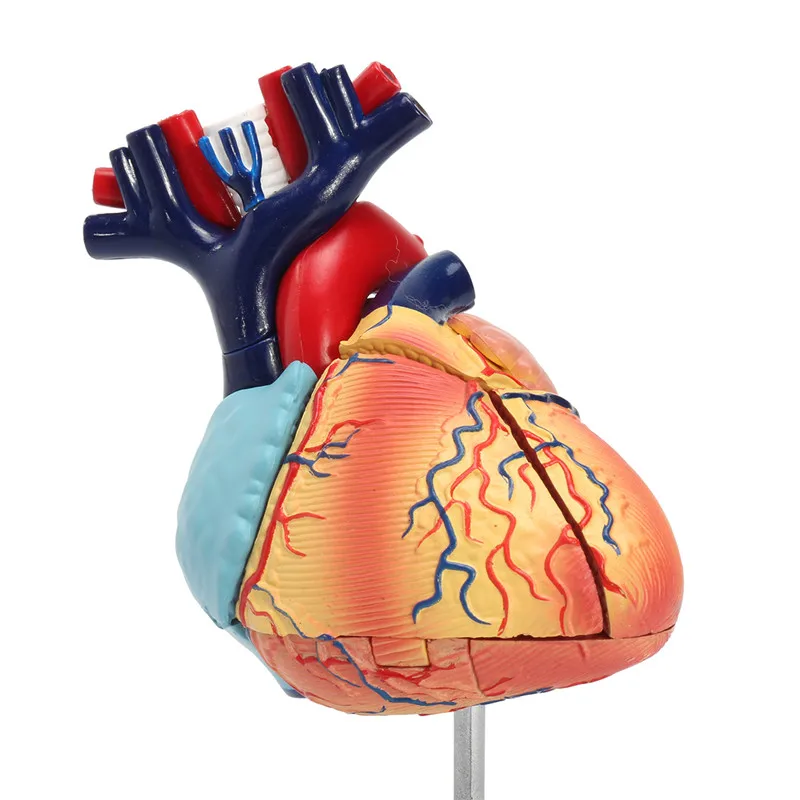

Фотографии и 3D-модели анатомии сердца человека